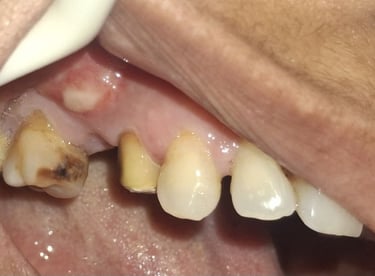

When Is Tooth Extraction Needed?

Tooth extraction may be recommended in cases of:

Severe tooth decay or infection

Broken or fractured tooth beyond repair

Advanced gum disease

All images shown here represent real clinical cases of teeth extractions done at our dental clinic with patient consent.

Illustrative images and similar real clinical cases requiring tooth extraction